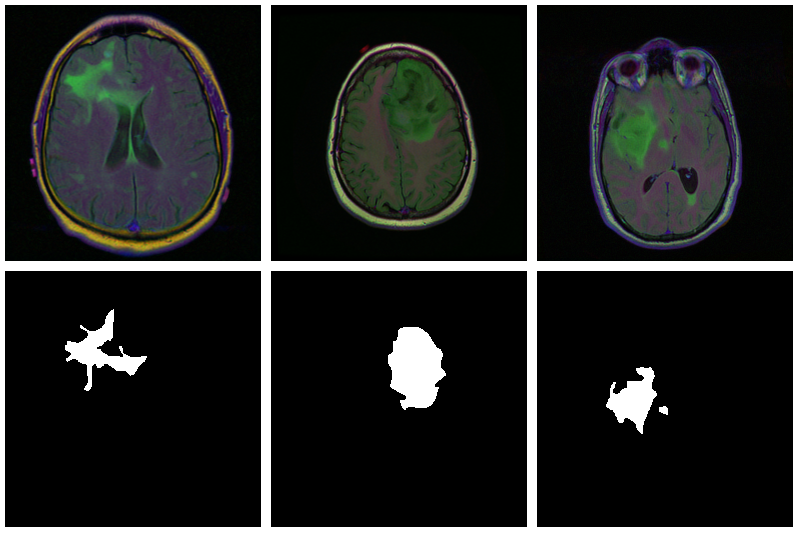

As is often the case in medical imaging, there is notable class imbalance in the data. For every patient, sections have been taken at multiple positions. (Number of sections per patient varies.) Most sections do not exhibit any lesions; the corresponding masks are colored black everywhere.

Here are three examples where the masks do indicate abnormalities:

Let’s see if we can build a U-Net that generates such masks for us.